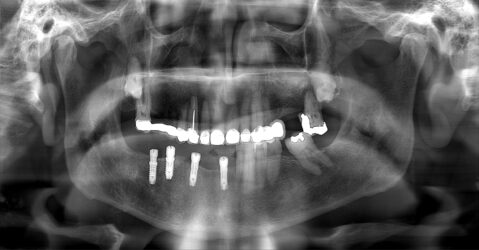

Hi I have an implant bridge case to restore. Pt is in his 80s. I have just been restoring single units before this and would love some help/advice about how to proceed. The initial idea was just to scan, which I’m comfortable doing. But I have learned that the scanner may not be so accurate for larger cases like this. I will order a special tray first of all.